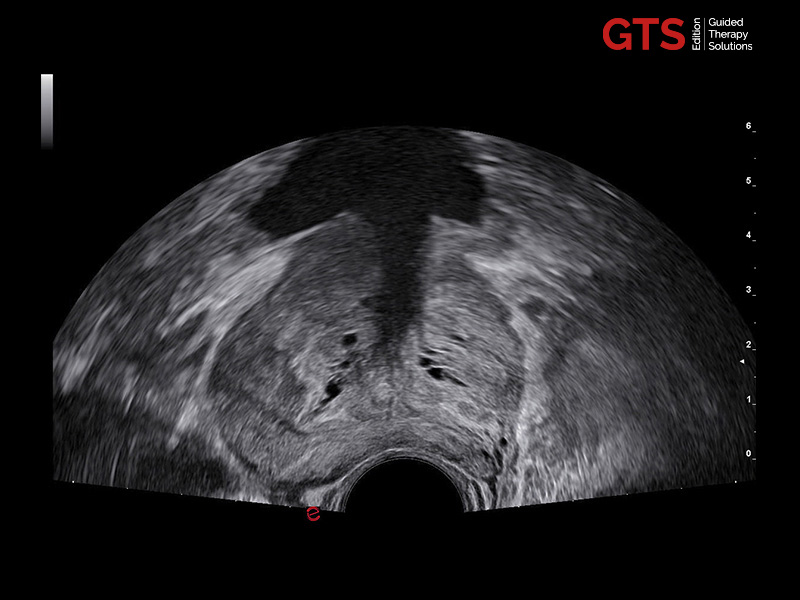

Prostate in axial view using E 3-12 - End-fire probe, E 3-12

Daily prostate examinations: Trans-Perineal Ultrasound (TPUS) and Trans-Rectal Ultrasound (TRUS) approaches

In daily practice, high image quality and ease of use of advanced features (with fast and automatic measurements) make the difference.

Our new urology solutions enhance the user experience and increase confidence by offering the option of performing detailed prostate examinations with either TRUS or TPUS biopsy approaches, thanks to our end-fire or bi-plane transducers. Each probe is compatible with tailored biopsy guides, either reusable or single use.